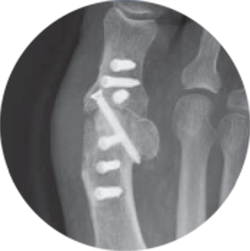

CoLink® PCR

Sistema de placas reforzadas de fibra de carbono

Invisible para rayos X, para que el hueso sea más visible

Ya que las placas son invisibles para los rayos X al contar con sulfato de bario para baja visibilidad, ofrecen una experiencia de diagnóstico por imágenes radiotransparente y libre de artefactos.